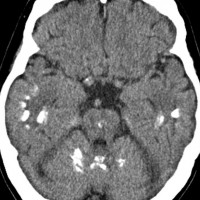

多房性白質壊死 multicystic white matter malacia

放射線により脳の髄鞘を形成する乏突起膠細胞 オリゴデンドロサイトoligodendrocyte (乏突起膠細胞)が障害を受け,脱髄 demyelinaiton が生じて白質脳症となります。上記の例はその病理像を反映するMRI所見です。

脳微小血管内皮細胞の放射線障害によって白質が小さな虚血性梗塞となり,白質壊死 white matter necrosisという重い白質脳症もあります。この場合は画像で脳の内部に穴の開いたような像(軟化巣)がみられます。上の画像は,35グレイの全脳照射を受けた5歳の子どものものです。左側が鞍上部ジャーミノーマの治療前のもの,右側は放射線治療2年後のものです。脳の中にたくさんの穴が開いています。これをのう胞性軟化巣 cystic malacia といいます。白質脳症の最も重いかたちのものです。